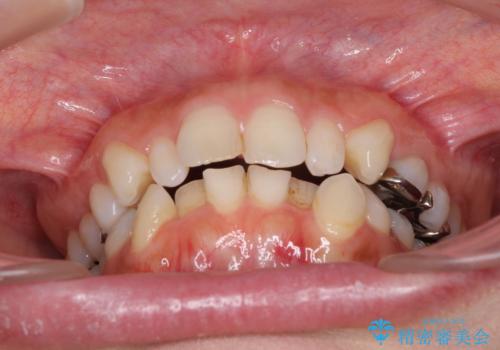

- 前歯のデコボコと矮小歯、更には痛みを感じる奥歯のむし歯を気にして来院された患者様です。

奥歯には根管治療が必要な歯があり、上顎側切歯は左右ともに矮小歯でした。

上下前歯のデコボコはワイヤーでもインビザラインでも対応可能でしたが、補綴治療が多く必要となることから、インビザラインでの矯正治療を行いながら、並行して補綴治療を行うこととしました。

まずは根管治療を行った上で矯正治療用の仮歯を装着し、矯正治療後半に補綴治療を並行して行うこととしました。